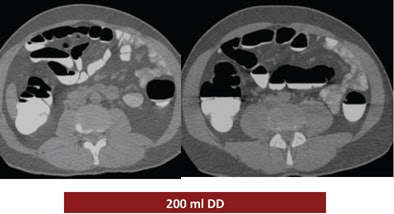

The study looked at three groups of 30 patients who underwent virtual colonoscopy after a same-day bowel preparation. Group 1 ingested 200 mL of undiluted DD the day of the exam, group 2 drank 100 mL of the agent the day of the exam, and group 3 ingested a low-dose polyethylene glycol (PEG) formula (macrogol) the two days before the exam, followed by 100 mL of DD the day of the exam.

| Above, the use of 200 mL DD in group 1 yielded the highest quality scores. While the colonic mucosa was well marked, significant volumes of fluid remained in the colon, similar to the 100 mL DD preparation (group 2, below). The use of 100 mL combined with low-dose polyethylene glycol over two days (bottom image) may have improved fecal tagging by softening the stool before the ingestion of DD. |